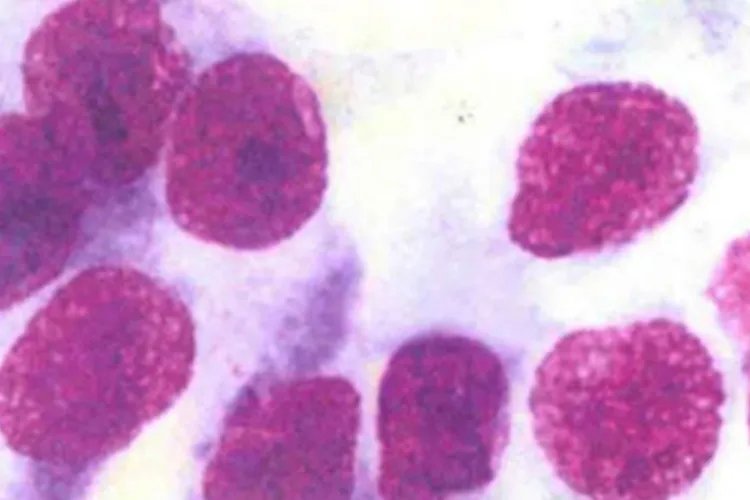

腺细胞癌来源于腺体、导管或分泌上皮细胞的恶变。腺癌细胞常成堆分布,呈桑葚状、花瓣状;胞质内常含有多少不等的黏液空泡,常将核挤于一侧,呈戒指状。与鳞癌细胞相比,核增大、核畸形、核深染、核质比增大不明显。一般根据细胞的分化程度将腺癌分为高分化腺癌和低分化腺癌。高分化腺癌胞体较大,大小不一,呈圆形、卵圆形,形态异形不明显,胞质丰富,可含有空泡,有时空泡将胞核挤于一侧,形成印戒样癌细胞;与鳞癌相比,核大、核畸形、核深染不明显。

低分化腺癌癌细胞多成堆、相互重叠,极性紊乱,易融合成团,胞体小;胞质少,呈嗜碱性,可有少量不明显的空泡;与高分化腺癌相比,核畸形、核深染明显。